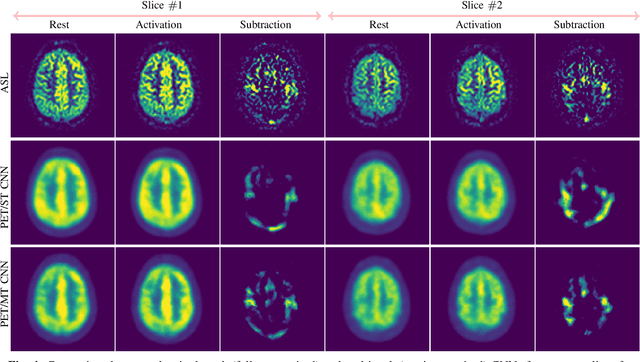

Abstract:Positron Emission Tomography (PET) is an imaging method that can assess physiological function rather than structural disturbances by measuring cerebral perfusion or glucose consumption. However, this imaging technique relies on injection of radioactive tracers and is expensive. On the contrary, Arterial Spin Labeling (ASL) MRI is a non-invasive, non-radioactive, and relatively cheap imaging technique for brain hemodynamic measurements, which allows quantification to some extent. In this paper we propose a convolutional neural network (CNN) based model for translating ASL to PET images, which could benefit patients as well as the healthcare system in terms of expenses and adverse side effects. However, acquiring a sufficient number of paired ASL-PET scans for training a CNN is prohibitive for many reasons. To tackle this problem, we present a new semi-supervised multitask CNN which is trained on both paired data, i.e. ASL and PET scans, and unpaired data, i.e. only ASL scans, which alleviates the problem of training a network on limited paired data. Moreover, we present a new residual-based-attention guided mechanism to improve the contextual features during the training process. Also, we show that incorporating T1-weighted scans as an input, due to its high resolution and availability of anatomical information, improves the results. We performed a two-stage evaluation based on quantitative image metrics by conducting a 7-fold cross validation followed by a double-blind observer study. The proposed network achieved structural similarity index measure (SSIM), mean squared error (MSE) and peak signal-to-noise ratio (PSNR) values of $0.85\pm0.08$, $0.01\pm0.01$, and $21.8\pm4.5$ respectively, for translating from 2D ASL and T1-weighted images to PET data. The proposed model is publicly available via https://github.com/yousefis/ASL2PET.